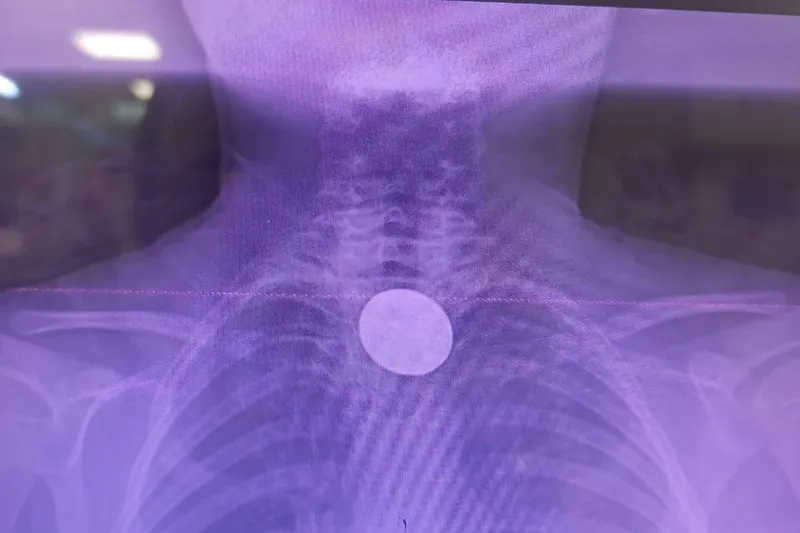

Siirt’te küçük çocuğun yuttuğu madeni para başarılı operasyonla çıkarıldı

Siirt’te 5 TL’lik madeni para yutan 8 yaşındaki çocuk, gastroenteroloji ve KBB uzmanlarının ortak müdahalesiyle sağlığına kavuştu. Olası hayati risk, başarılı operasyonla önlendi.

Siirt’te yaşayan 8 yaşındaki Y.K., boğazına madeni para kaçması sonucu ailesi tarafından Siirt Eğitim ve Araştırma Hastanesi’ne götürüldü. Yabancı cisim yutma şikâyetiyle acil servise başvuran küçük hasta, yapılan ilk muayene ve görüntüleme tetkiklerinin ardından hızla değerlendirmeye alındı.

Madeni paranın yemek borusuna kadar indiği tespit edildi

Yapılan incelemelerde 5 TL’lik madeni paranın Y.K.’nin yemek borusuna kadar ilerlediği belirlendi. Çocuk hastalarda ciddi solunum ve sindirim sistemi riskleri oluşturabilen bu durum üzerine ilgili branşlar vakit kaybetmeden harekete geçti.

Gastroenteroloji ve KBB’den ortak operasyon

Madeni paranın çıkarılması için Gastroenteroloji Uzmanı Dr. Yaren Dirik ile Kulak Burun Boğaz (KBB) Hekimi Dr. Yasin Gökçınar tarafından ortak bir girişim gerçekleştirildi. Alanında uzman ekiplerin koordineli çalışmasıyla madeni para herhangi bir komplikasyona yol açmadan başarıyla çıkarıldı.

“Operasyon sorunsuz geçti, hastamızın durumu iyi”

Siirt Eğitim ve Araştırma Hastanesi Başhekim Yardımcısı Uzman Dr. Burak Özkan, operasyonla ilgili yaptığı açıklamada çocuklarda yabancı cisim yutma vakalarının hayati riskler taşıyabileceğine dikkat çekerek şunları söyledi:

“Hastanemize başvuran 8 yaşındaki hastamızın yemek borusuna kaçan madeni para, gastroenteroloji ve KBB ekiplerimizin koordineli çalışmasıyla başarılı bir şekilde çıkarılmıştır. Operasyon süreci sorunsuz geçmiş olup hastamızın genel durumu iyidir.”

Tedavisi tamamlandı, sağlıkla taburcu edildi

Operasyonun ardından bir süre gözlem altında tutulan küçük hastanın genel sağlık durumunun iyi olduğu, herhangi bir ek soruna rastlanmadığı bildirildi. Y.K., gerekli kontrollerin tamamlanmasının ardından sağlıklı bir şekilde taburcu edildi. (İLKHA)